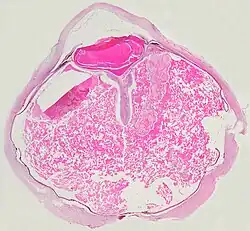

Choroba Coatsa (łac. teleangiectasis retinae, morbus Coats, ang. Coats' disease, exudative retinitis, retinal telangiectasis) – wrodzone, niedziedziczne, postępujące uszkodzenie naczyń krwionośnych siatkówki. Choroba może przypominać przebiegiem siatkówczaka[2]. Schorzenie opisał jako pierwszy szkocki okulista George Coats w 1908 roku[3].

W ciężkich postaciach choroba objawia się masywnymi wysiękami z wtórnym odwarstwieniem siatkówki. Może wystąpić biały refleks źreniczny (leukokoria), zez i niedowidzenie. W lżejszych postaciach objawem jest obniżenie ostrości wzroku.

- 1 2 3 Fernandes BF, Odashiro AN, Maloney S, Zajdenweber ME, Lopes AG, Burnier MN Jr. Clinical-histopathological correlation in a case of Coats' disease. „Diagn Pathol”. 1. 24, 2006. DOI: 10.1186/1746-1596-1-24. PMID: 16942617.

- Fernandes BF, Odashiro AN, Maloney S, Zajdenweber ME, Lopes AG, Burnier MN Jr. Clinical-histopathological correlation in a case of Coats' disease. „Diagn Pathol”. 1. 24, 2006. DOI: 10.1186/1746-1596-1-24. PMID: 16942617.